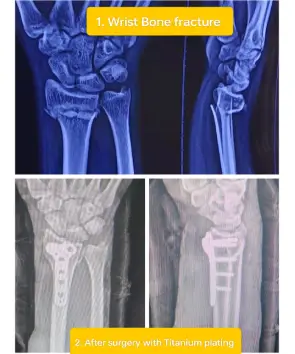

Dr. Keerthivasan Contact number WhatsApp